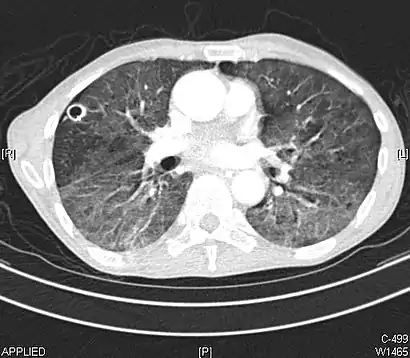

CT image showing mosaic attenuation pattern in patient with hypersensitivity pneumonitis. Note the alternating, patchy areas of increased and decreased attenuation, particularly in the left lung (screen right).